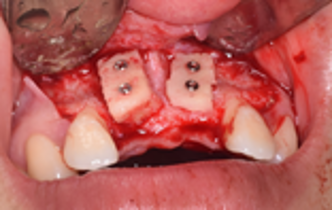

Ghép xương tự thân

Phục hình trên bệnh nhân cắt đoạn xương hàm và ghép xương tự thân